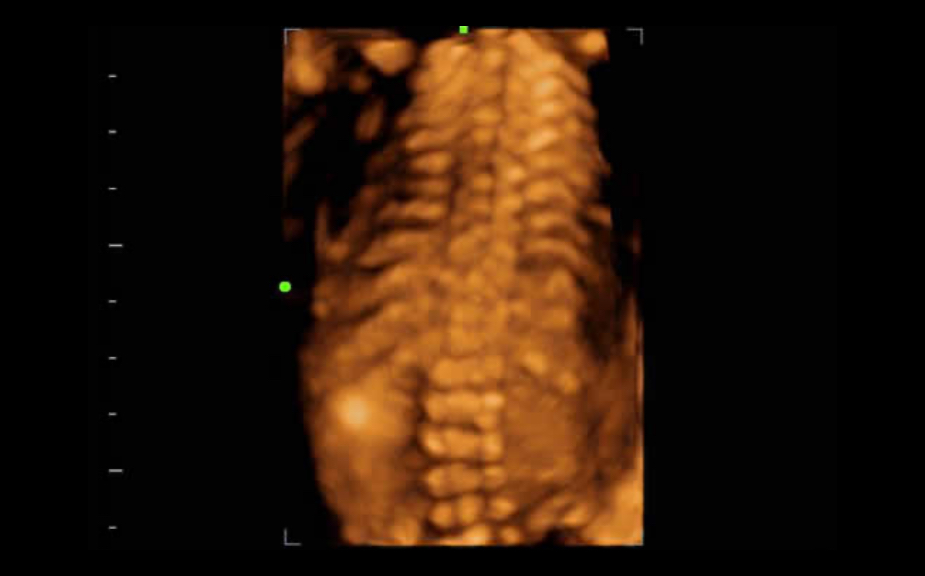

3B/4B G?rÞntÞleme

G?rÞntÞnÞn her y?nden h?zl? ve kolay bir ?ekilde izlenebilmesini sa?layan 3B/4B ?evirme ve E?itleme ?zelli?i ile

iLive

Ray-casting algoritmas?n? yeni sanal ???kland?rma modalitesi ile entegre eden iLive, insan derisine benzer g?rÞntÞlerle fetÞsÞn son derece ger?ek?i bir g?rÞnÞmÞnÞ olu?turur.